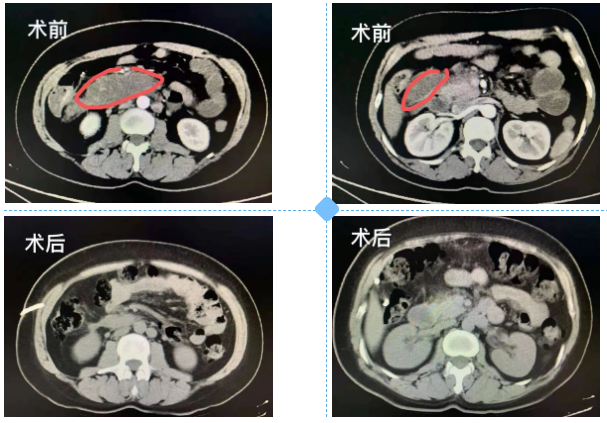

外院ERCP术后胰腺炎胰头后下方渗出感染症状明显(不排除腹膜后穿孔),来到我院后在超声引导下择点避开肠管,置两条双腔猪尾巴管(8.5Fr、12Fr)冲洗引流,一周后带管出院,两周复查完全好了,今拔管,医患均甚是高兴。